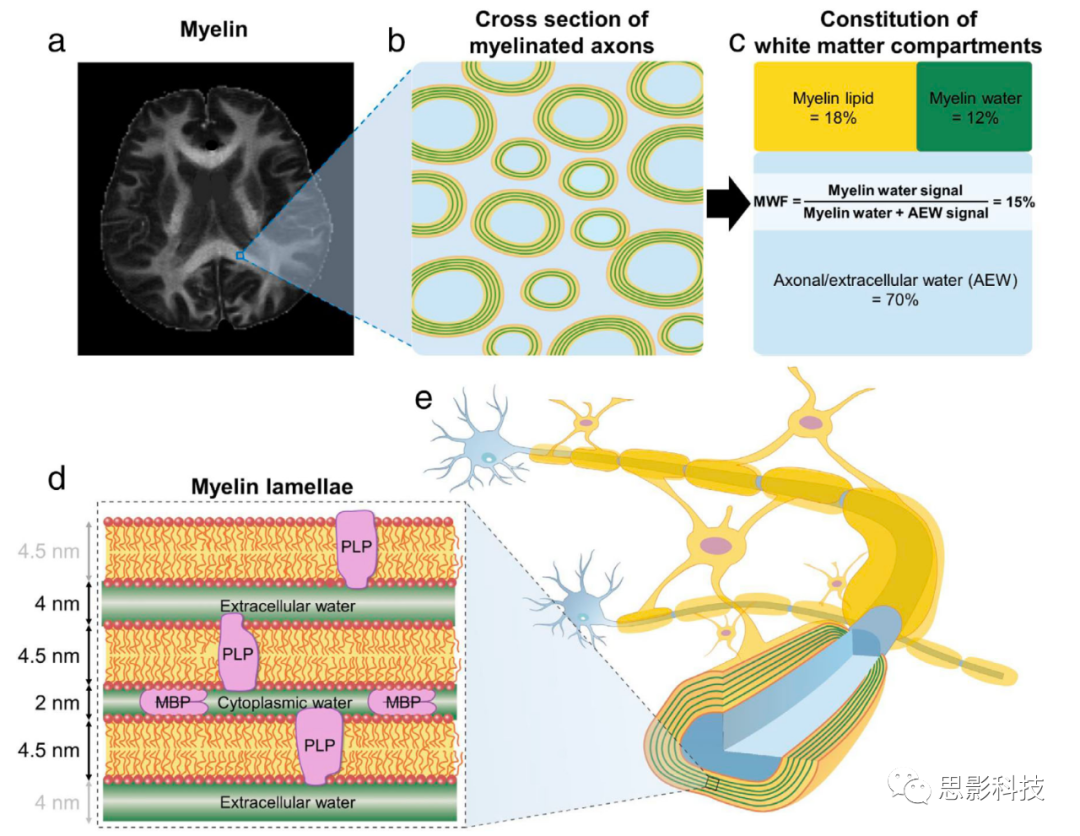

答案1: 髓鞘是一种富含脂质的组织,它在神经纤维周围形成绝缘层(图1)。在中枢神经系统(CNS)中,髓鞘的水分含量约为40%。髓鞘的干重约为70%的脂质和30%的蛋白质。髓鞘的脂质成分包括胆固醇、脑苷脂和各种磷脂。对于蛋白质,脂质蛋白(PLP)和髓鞘基本蛋白(MBP)分别占髓鞘蛋白的50%和30%。 CNS中的髓鞘是由少突胶质细胞产生的。一个少突胶质细胞可以髓化多达50个轴突。每个髓鞘包裹轴突的一个段落多次。髓鞘包裹的这种独特超微结构已经使用电子显微镜进行了研究,并揭示了一个交替的电子致密层和轻层的层状结构。这个层片的周期性约为14纳米,夹在两个脂质双层(每个4.5纳米宽)之间的2纳米宽的细胞质水和4纳米宽的细胞外水(图1d)。在MWI( 髓鞘水成像)中,两层水中的水质子被称为髓鞘水,并被认为是髓鞘水信号的来源。层片的平均数量被报道为15。髓鞘鞘的长度在500和2000微米之间。在两个相邻的髓鞘鞘之间,存在一个1微米的小间隙,被称为Ranvier结。这个裸露的轴突膜允许离子交换,并在跳跃传导中起到关键作用,加速动作电位的信号传导。与传导速度为0.5-2.0米/秒的未髓化轴突相比,髓化轴突可以以传导速度高达70-120米/秒传递动作电位。除了这个重要的作用,髓鞘还被建议对神经可塑性(例如,活动依赖性髓鞘可塑性影响神经功能)和轴突的代谢支持。因此,髓鞘是大脑正常功能的关键物质。

图1:大脑中的髓鞘和髓鞘水图像。

(a) 大脑中髓鞘的概念图像。

(b) 髓化轴突的横截面(浅蓝色:轴突/细胞外水(AEW),绿色:髓鞘水,黄色:脂质)。

(c) 白质区室构成的一个例子。髓鞘水分数(MWF)被定义为髓鞘水信号与总水信号的比率,其中包括髓鞘水和AEW水信号。

(d) 髓鞘层片的放大视图。髓鞘具有高度规则的层状结构,有两个脂质双层(每个4.5纳米)和一个细胞质水层(2纳米)形成多个包裹。包裹之间存在一个细胞外水层(4纳米)。

(e) 带有髓化轴突的神经元的概念图。